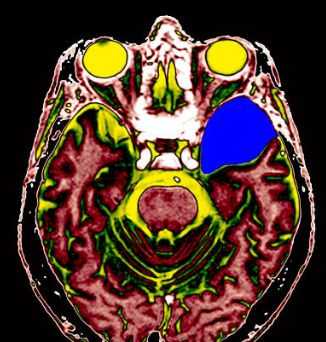

МРТ головного мозга. Арахноидальная киста полюса левой височной доли. Цветовая обработка.

Кисты головного мозга - это аномалии его развития. При МРТ в СПб мы видим задачу в дифференциальной диагностике с кистозными формами опухолей. При МРТ головного мозга некоторые виды кист, особенно дермоидные, сами напоминают опухоль.

Арахноидальные кисты представляют собой скопление ликвора между листками расщепленной паутинной оболочки. Арахноидальная киста обычно не сопровождается другими мальформациями. Незначительная часть арахноидальных кист имеет приобретенное происхождение - следствие лептоменингита, операции или кровоизлияния. Частота составляет около 1% от внутричерепных образований. Соотношение полов М:Ж, как 4:1. Типичная локализация - средняя черепная ямка (в области Сильвиевой борозды 50%), межполушарная щель, мосто-мозжечковый угол (11%), за скатом или на уровне четверохолмия (10%), в области червя мозжечка (9%), реже в области межножковой и предмостовой цистерн (3%), а также супраселлярной и хиазмальной цистерн. В зависимости от размера предложено делить кисты на 3 типа (Galassi, 2006), что однако, не имеет практического значения. Ретроцеребеллярная арахноидальная киста довольно часто встречаются за мозжечком и отличима от mega cisterna только по неизменённой задней черепной ямке. При МРТ головного мозга содержимое кисты чисто ликворное, стенки гладкие, чётко очерченные, внутри кисты могут быть перегородки. Мелкие арахноидальные кисты очень трудно увидеть при МРТ головного мозга. Меняя ширину окна и его уровень на Т1-зависимых МРТ изображениях можно заметить, что киста чуть светлее ликвора. Дифференциальная диагностика с эпидермальными кистами лучше осуществляется с помощью МРТ последовательности FLAIR. На них при МРТ головного мозга эпидермальные кисты становятся яркими, в отличие от гипоинтенсивных арахноидальных. Вероятно, вариантом арахноидальной кисты является нейроэпителиальная киста, которая при МРТ головного мозга имеет типичное расположение в области хориоидальной щели.